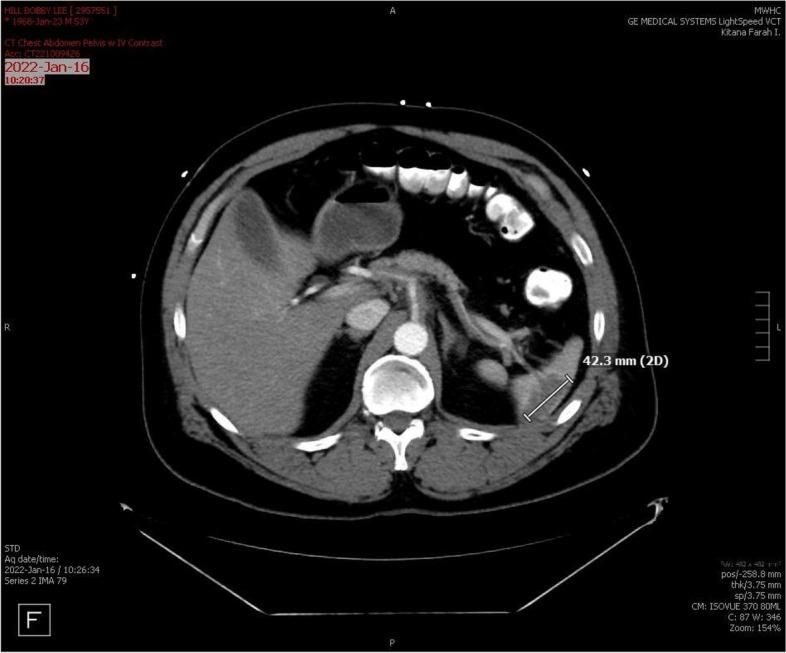

结节性多动脉炎(PAN)是一种系统性血管炎(SV),历史上被认为不会累及冠状动脉。冠状动脉造影和现代影像学显示冠状动脉狭窄和扩张,这与显著的发病率和死亡率相关。PAN 中的冠状动脉受到全身炎症引起的加速动脉粥样硬化的影响,这增加了固有动脉炎过程的风险。传统的动脉粥样硬化危险因素无法准确估计风险。很少有报道描述冠状动脉的病理变化,最佳治疗方法也受到限制。

冠状动脉受累的严重程度难以通过实验室监测来评估,但冠状动脉疾病与几种临床症状相关。弗雷明汉危险因素不能充分估计疾病负担。要将动脉粥样硬化与动脉炎分开,需要先进的血管造影方法。治疗包括抗凝、免疫抑制和血运重建。经皮冠状动脉介入治疗(PCI)一直是主要的治疗方法,尽管支架置入后由于管腔直径的不规则变化和新生内膜形成的报告,支架的应用受到限制。

当移植物选择避开 SV 的血管区域时,冠状动脉旁路移植术(CABG)提供了明确的治疗方法。除了回顾、更新和讨论文献外,我们还报告了一种新型的 CABG 构型。越来越多的证据表明,特定的临床症状提示存在冠状动脉受累。